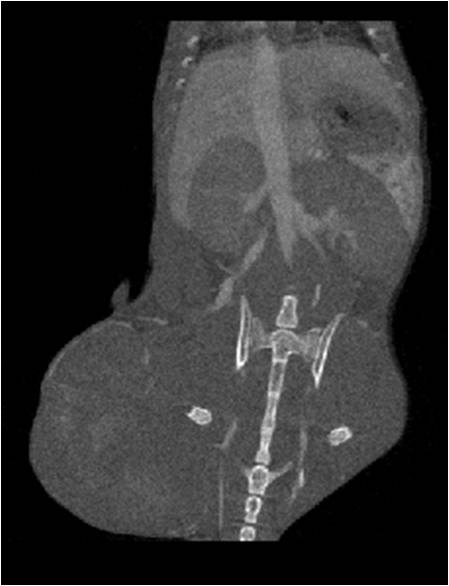

腫瘤血管生成

肺轉(zhuǎn)移

小鼠模式,22.5μm像素

正常

8天 14天

無造影劑注入 造影劑注入